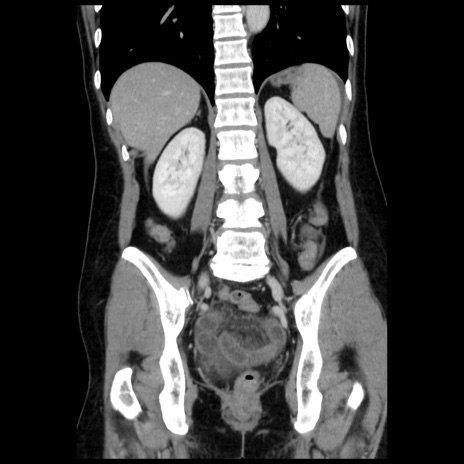

症例10(冠状断像)

【症例】 50歳代女性

【主訴】 腹痛

【現病歴】前日生レバーを食べた。今朝に排便あり。 昼前に突然発症の腹痛を生じ、当院救急外来を受診した。

【既往歴】 子宮筋腫にてで子宮全摘後

【身体所見】 意識清明、腹部:平坦、軟、下腹部やや左を中心に圧痛・反跳痛あり、筋性防御あり

【データ】WBC 7800、CRP 0.07